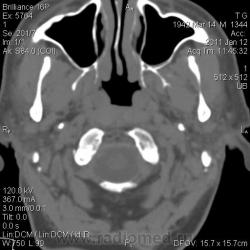

КТ-динамика после комбинированной терапии, 6 месяцев после первичной КТ:

Хорошие новости:

после прохождения пациентом 2 курсов химиотерапии и 33-кратной лучевой терапии (66 Гр), динамика просто потрясающая. И прошу прощения за невольное введение в заблуждение по поводу клеточек, там не лимфома, а плоскоклеточный рак. Не то меня, не то пациента переклинило.

Иллюстрации контрольного исследования добавлены наверху.

Она была при первичном исследовании. Самой опухоли словно и нет. Свод носоглотки спокоен, нормализовалось носовое дыхание. Только последствия лечения в виде выраженной сухости во рту.